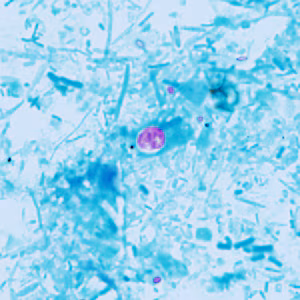

A 42-year-old dairy farmer sought medical attention for watery diarrhea, fever, and nausea that he had been experiencing for about one week. A stool specimen was collected for ova-and-parasite (O&P) work-up that included a formalin ethyl-acetate concentration. A fecal smear was prepared from the concentrate and stained with Kinyoun’s modified acid-fast stain. Figures A–E show what was observed at 1000x magnification with oil in moderately high numbers on the acid-fast stained fecal smear. The stained objects measured 5 micrometers in diameter on average. What is your diagnosis? Based on what criteria? What, if any, other tests would you recommend?

Figure A